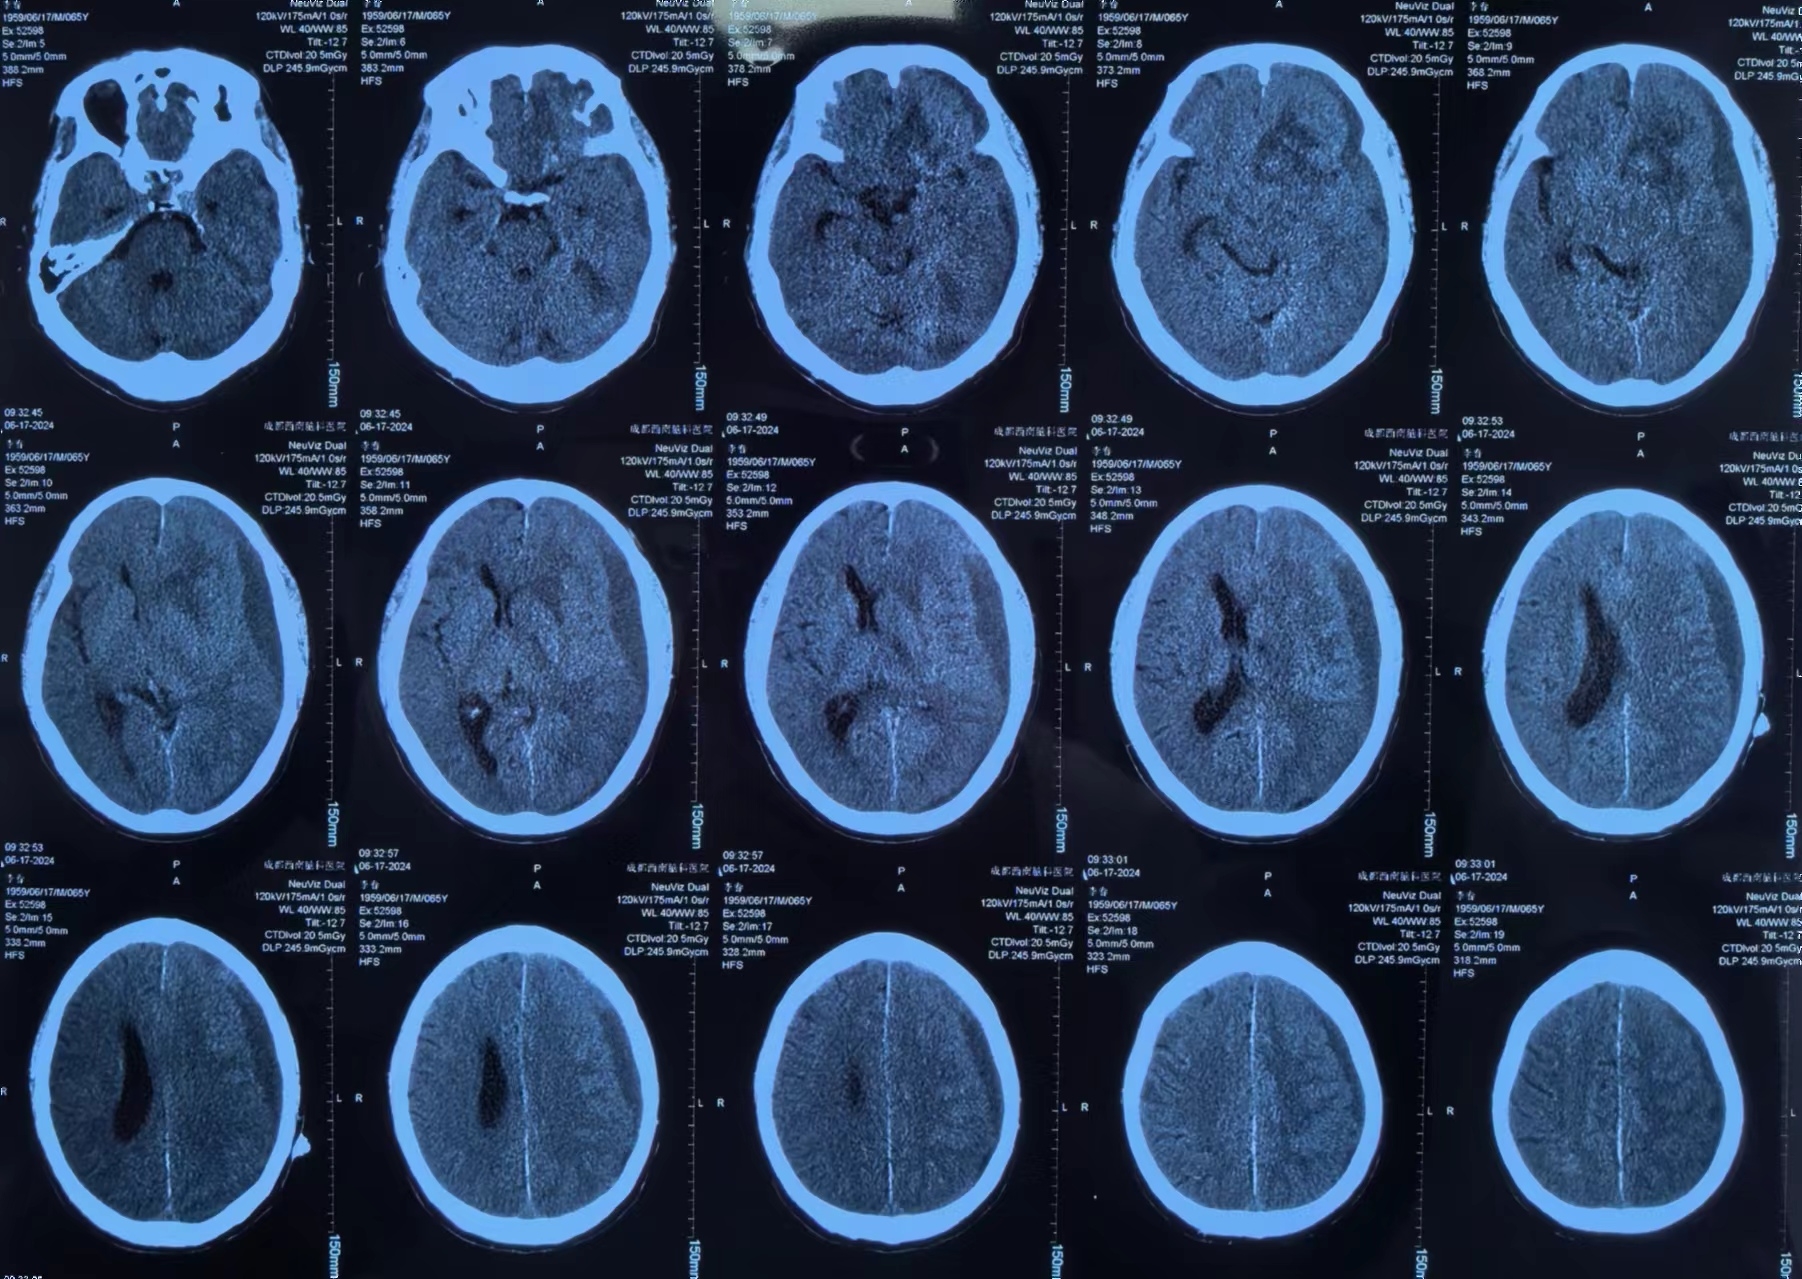

李先生手术前

术后李先生自觉头痛明显减轻,术后第三天复查头颅CT提示:硬膜下血肿基本清除,脑移位恢复正常。